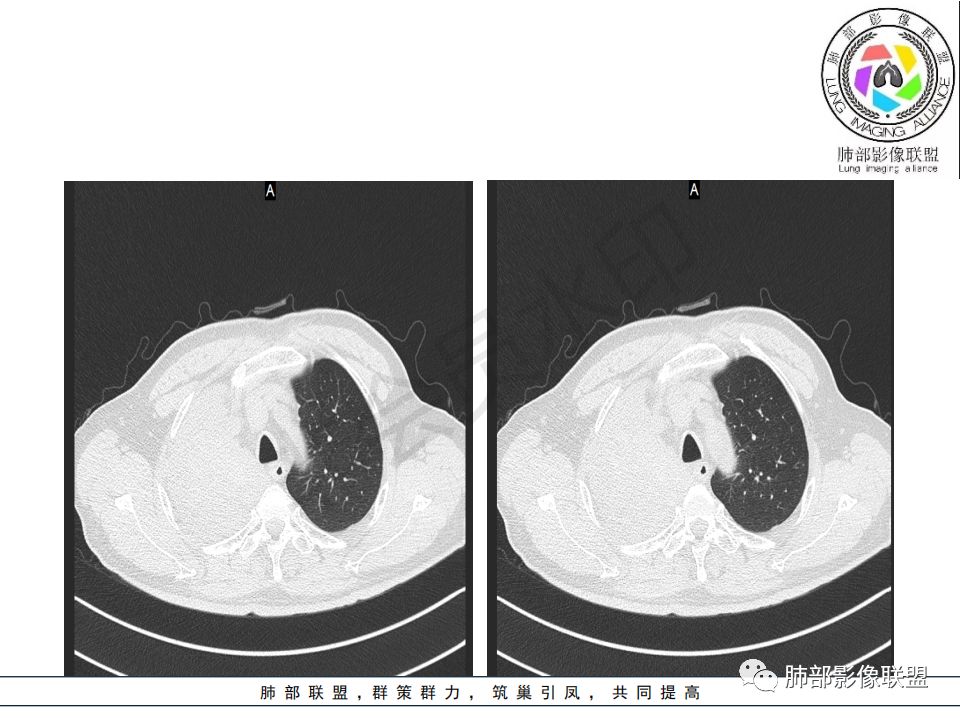

右肺主支气管内外软组织影,支气管变窄截断,右肺上叶成软组织密度,其内见细沙样钙化,周围看见小结节,右肺门看见一淋巴结稍大,增强不均匀强化,胃癌病史,考虑:转移,或原发肺恶性鳞癌。

影像:影像右侧大支气管阻塞,临床没有症状或很轻微,要想到胃腺癌转移;胸壁代偿好,透亮度稍低不明显,慢性过程;34.8-52.5HU,主病灶支气管前壁另有1结节,都做成增强两期了,动脉期较平扫有强化;

右肺上叶肿块,边缘光滑,略膨隆,近段支气管堵塞,平扫密度均匀,增强后不均匀强化,其内可见不规则血管和坏死,纵隔淋巴结肿大,老年男性,无感染性病史,综合考虑恶性肿瘤(鳞癌,腺癌),鉴别:OP(一般下叶多见)

晨读病例:老年男性,症状轻,右侧胸廓略塌陷,右肺主支气管内外软组织影,支气管变窄截断,右肺上叶不张,其内见细砂样钙化,周围看见小结节,右肺门看见一淋巴结稍大,增强不均匀强化,胃癌病史,常规考虑:转移,或原发肺恶性鳞癌。鉴别支气管TB?

从强化情况和冠状位看主要还是从外向内的一个肿块,有不张,但不张范围不大,近端支气管堵塞,考虑腺癌或类癌(原发或转移都可能),鉴别鳞癌。

1.右肺上叶较大块影,密度不均,轻度强化并见低密度区,所属支气管截断并腔内突入,是符合肺鳞癌的影像学特征和生物学行为的。